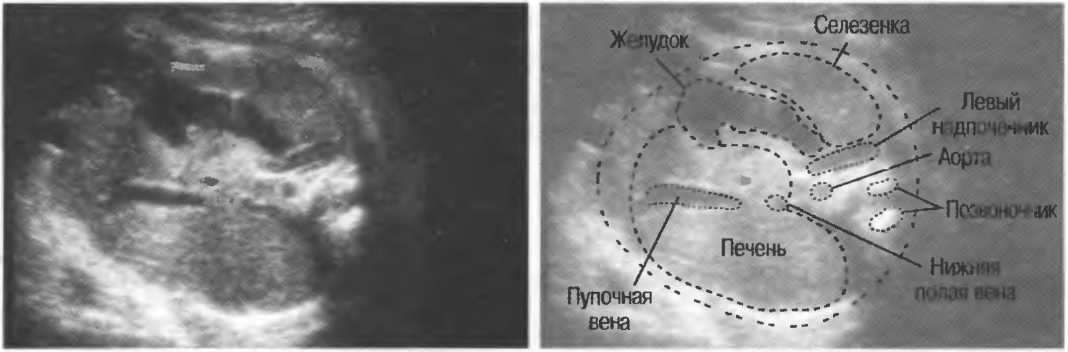

Рис.5. Два поперечных среза плода, демонстрирующих тень от позвоночника плода. Аналогичная тень от ребер может частично закрывать почки или печень. Изменяя угол наклона датчика, можно изменить положение тени таким образом, чтобы подлежащие ткани были видны отчетливо.